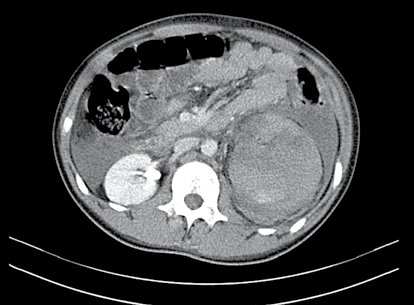

Paciente, vítima de acidente de moto, atendido pelo SAMU, chegou ao pronto-socorro de hospital terciário, consciente, queixando-se de dor na região lombar e flanco esquerdo. Tinha recebido previamente 1 000 mL de Ringer-lactato. Ao exame, mucosas pouco descoradas, sem cianose, PA: 130/80 mm/Hg, FC: 96/min., rítmico. Abdome não distendido, doloroso no flanco e região lombar esquerda com hematoma superficial e escoriações no local. A sondagem vesical realizada sem dificuldades apresentou 150 mL de urina “concentrada”. Permaneceu em observação e, devido às condições hemodinâmicas estáveis foi submetido à tomografia computorizada abdominal.

Diante da imagem apresentada e do contexto anterior, pode- se afirmar que se trata de: